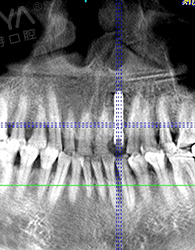

我很信任鄭教授帶領的種牙團隊,而且現在不比當年了,科技也發達了,尤其是麥芽口腔的環境、設備這些都感覺很高大尚,拍個片子都是三維的,不到10分鐘,片子就呈現在醫生的電腦上了,在幾十年前哪有這種設備啊。

鄭院長帶領的醫師團隊,給我講片子很清楚,說我的左上2牙齒出現鬆動,但是牙齦狀況良好,可以告訴我牙齒即拔即種,無需等待3個月拔牙癒合期,避免二次創傷性傷口,他們以修復為導向,尤其我這種前牙的,還要兼顧咀嚼的咬合功能與美觀性,雖然不太懂這個科技, 但我還是很信賴鄭院長的團隊的,也感歎現在科技的先進。 方案定制完成後,3D口掃取模,就跟牙刷大小一樣的東西在口內掃一下,為了製定導板,種牙的時候更方便。